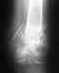

Re: Перелом беровой кости со смещением

Действительно, лучше сделать операцию. Конструкции могут быть использованы разные, даже не только пластины. Выбор зависит и от того, с какими конструкциями хирург лучше знаком.